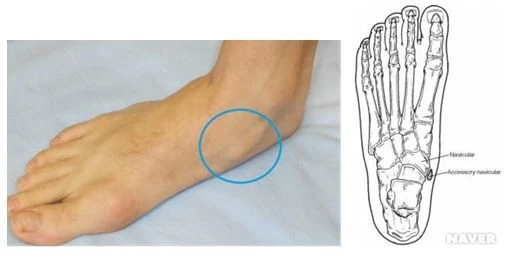

가만히 보고 있자니 발목 안쪽에 뼈가 튀어나오는 열명 중 한명꼴로 나타난다는 "부주상골증후군"으로 보였다.

아이의 양쪽 발목을 보니 이곳이 툭 튀어나와 있는게 아닌가!

누를때마다 아프다고 한다. ㅠㅠ

"부주상골증후군 같아요. 왜 지난번 진료에서 발견을 못했을까요?"

그리고 부주상골증후군 맞다는 이야기도 덧붙였다.